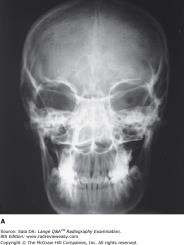

Posteroanterior projection

purpose of posteroanterior projection

Used to evaluate trauma; demonstrates frontal sinuses, orbit and nasal cavity